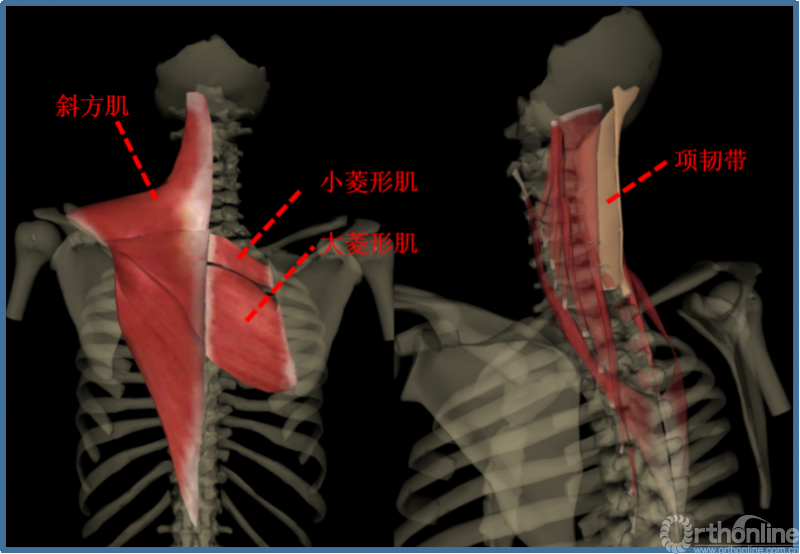

肌肉:

①项背肌分为两层:浅层为斜方肌、菱形肌。深层是颈背部固有肌,长肌在外,短肌在内,共分四层:夹肌、竖脊肌、横突棘肌、枕下肌、横突间肌和棘间肌。

②伸肌装置(中下颈椎)包括斜方肌、夹肌、竖脊肌中的头棘肌和颈棘肌、横突棘肌中颈半棘肌和头半棘肌、棘间肌。附着于棘突及椎板上的颈半棘肌、多裂肌是维持颈椎生理前凸的主要姿势肌群,而以头半棘肌为主的颈伸肌群又是维持颈椎动态稳定的主要因素。

③肌肉韧带复合体:颈半棘肌在颈2棘突下半部宽大的止点+项韧带。是维持颈椎静态和动态稳定的重要结构。